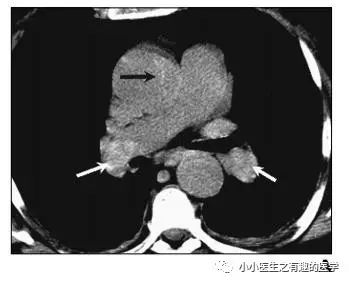

不光是肺栓塞,连主动脉夹层,都发现了。

牛。我来标记一下。

另外,CT发现肺纹理减少,也要警惕肺栓塞。先来说说马赛克。

假如CT平扫发现肺部某些地方血管稀疏,灌注不够,千万不要以为没事,有时候,就是肺栓塞,需要警惕。

马赛克,需要警惕肺栓塞,它是肺栓塞的间接表现。并且,在临床中,间断会遇到这样的情况。